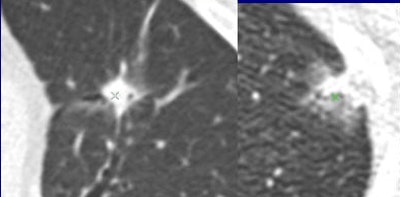

Are these nodules malignant or benign? The algorithm was confident for predicting the top-row lesions (correct responses) and the first lesion (left side) in the bottom row, but not confident for the last two lesions in the bottom row (middle, right). Results are anecdotal because the outcome depends on system operating point. (Answers left to right, top row followed by bottom row: malignant, benign, malignant, benign, malignant). All images courtesy of Dr. Anthony Reeves.

Are these nodules malignant or benign? The algorithm was confident for predicting the top-row lesions (correct responses) and the first lesion (left side) in the bottom row, but not confident for the last two lesions in the bottom row (middle, right). Results are anecdotal because the outcome depends on system operating point. (Answers left to right, top row followed by bottom row: malignant, benign, malignant, benign, malignant). All images courtesy of Dr. Anthony Reeves.The results showed only modest improvements versus size-based classification, but the work breaks new ground by taking the single most important predictor of malignancy by taking size out of the equation to focus on features alone.